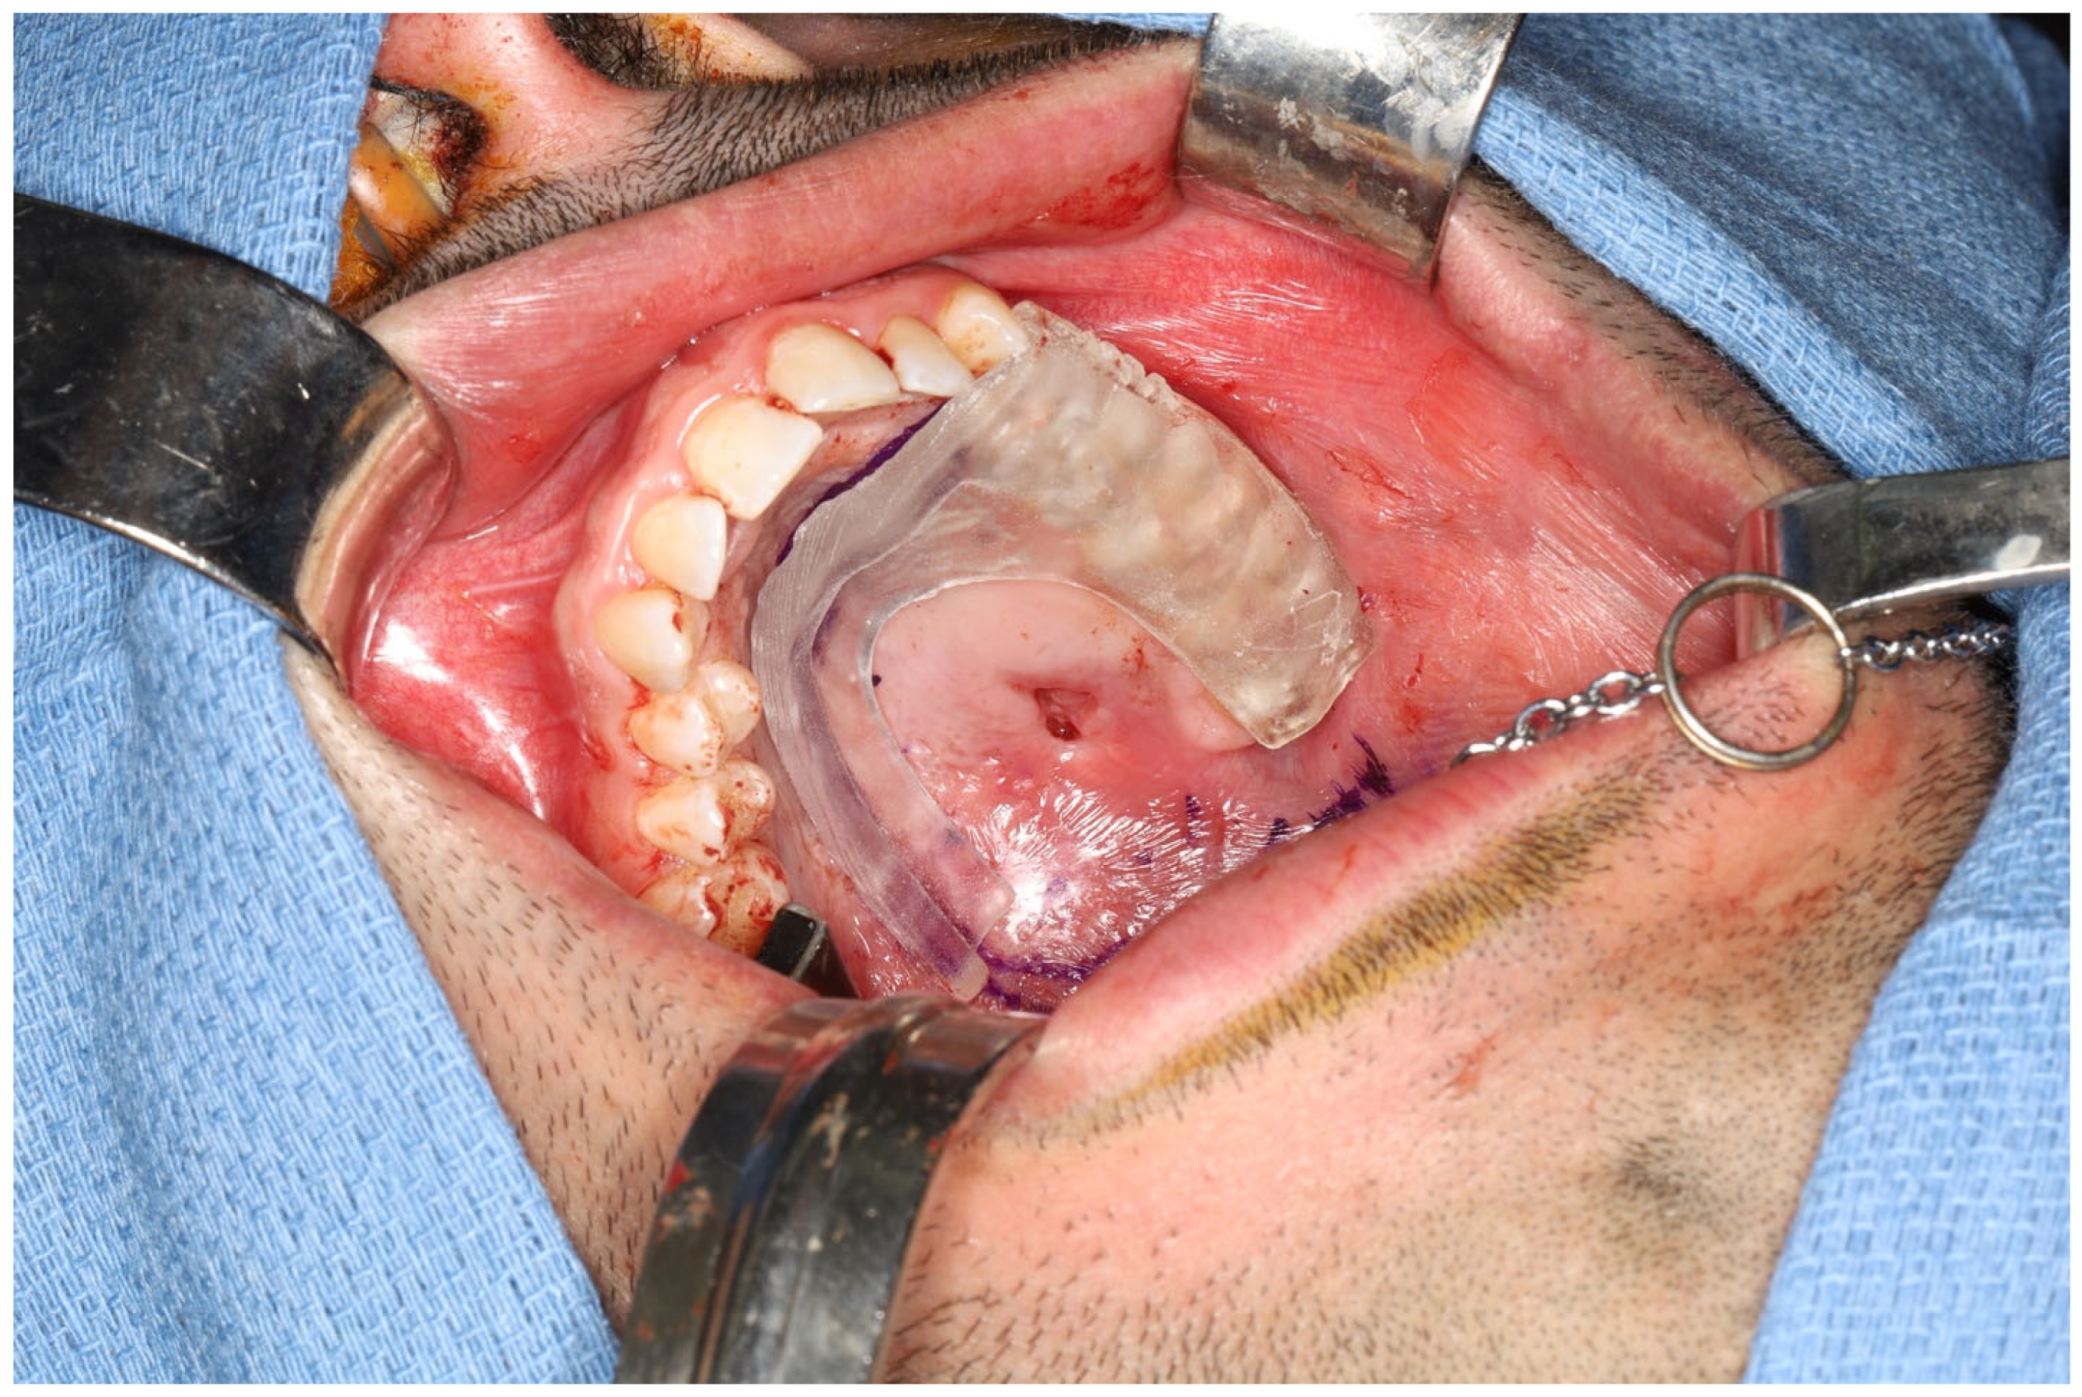

- Pre-perforation verification: After free flap harvesting and insetting, palpate the abutments over the zygomatic implant just before perforating the flap to ensure proper alignment of the planned perforation site.

- Flap Perforation: Create a stab incision with a #11 blade and gently dilate with fine Mosquito forceps. Avoid over-enlarging the perforation, maintaining soft tissue tension to allow abutment insertion while preventing outward displacement. Use sutures as needed to reinforce tissue tension around the abutment.